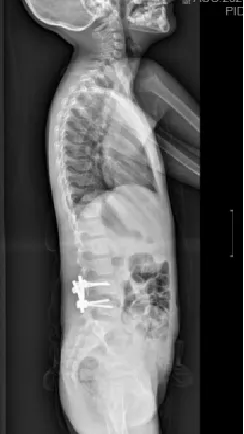

▲ 女,12岁,特发性脊柱侧凸、先天性脊柱畸形

▲ 女,14岁,青少年特发性脊柱侧凸